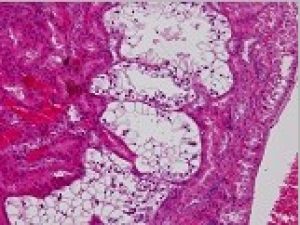

Carcinogenic mechanism of NDMA-induced renal tumorigenesis in SD and F344 rats

(Takamasa Yanagida)

Renal cell carcinoma

Adenoma